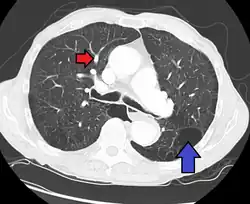

CT scan

Pulmonary artery hypertension and emphysema as seen on a CT scan with contrast

Signs of pulmonary hypertension on CT scan of the chest are:

• Increased ratio of the diameter of the main pulmonary artery (pulmonary trunk) to the ascending aorta (measured at its bifurcation).

• A ratio of 1.0 is suggested as a cutoff in adults.[63]

• Cutoff ~1.09 in children.[63]

• Increased diameter ratio of segmental arteries to bronchi. This finding in three or four lobes, in the presence of a dilated pulmonary trunk (≥29 mm), and absence of significant structural lung disease confers a specificity of 100% for pulmonary hypertension.[63]

• Mural calcification in central pulmonary arteries is most frequently seen in patients with Eisenmenger's syndrome.[63]